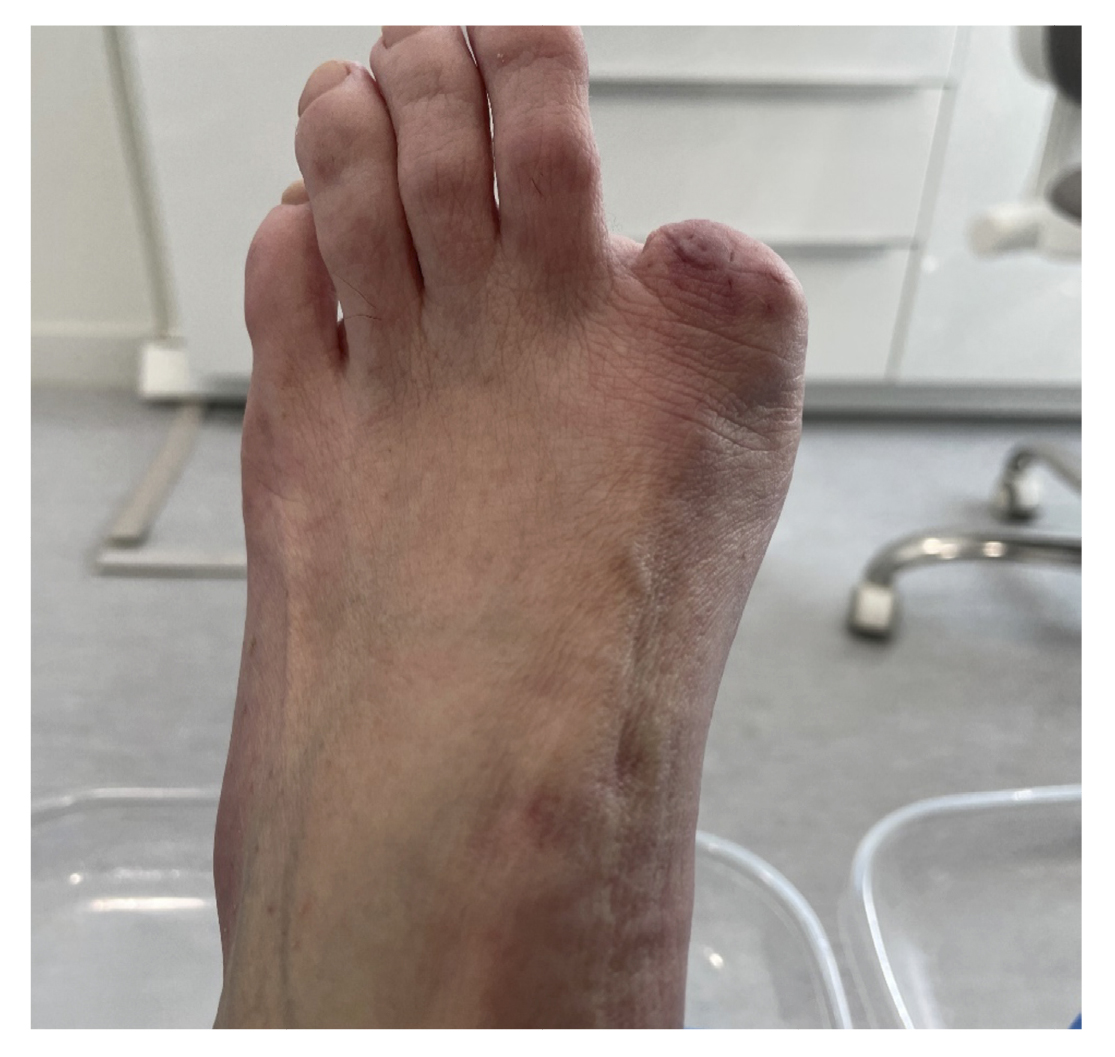

The patient reported a 7-month history onychocryptosis (September 2022) on the medial border of the first toe of the left foot, with presence of ungual granulation tissue on said border, causing her pain and digital inflammation (Figure 1). The patient received treatment from her podiatrist consisting of chiropody and canal cleaning, and then daily dressings with mupirocin were prescribed for the lesion. The lesion showed poor progression in the following days with increased pain and tenderness to the touch. Treatment was modified to amoxicilin/clavulanic acid 875/125 mg, 1/8 hours along with the use of oral analgesics (Figure 2). The patient continued with poor symptomatic evolution and attended her health center where an X-ray was performed, ruling out the presence of deep infection (osteomyelitis).

Figure 1. Initial process of onicochryptosis and reactive granuloma.

Figure 2. Clinical progressión after antibiotic and analgesic treatment.